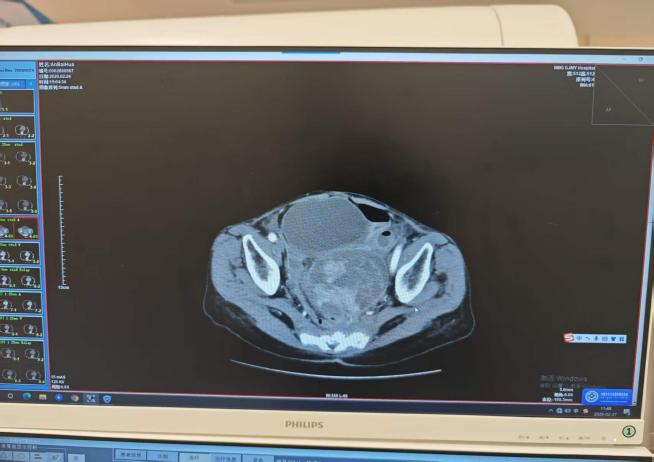

术后造影图